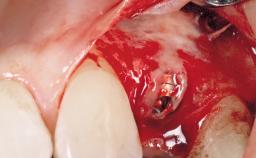

Immediate Flapless Placement of an Implant in a Maxillary Right Lateral Incisor Site

This 43-year-old male patient, a non-smoker, came to our practice because of a fracture of tooth 12 caused by a bicycle accident. Due to the combined para- and infrabony crown and root fracture, tooth extraction, and subsequent implant placement were suggested to the patient as the therapy of choice. The patient had high esthetic expectations with regard to the treatment outcome and asked for an immediate fixed provisional restoration. His individual esthetic risk profile summed up to a medium esthetic risk.

Placement Protocol Immediate implant placement

Tooth Site Maxillary incisor or canine

Socket Morphology Single-root socket

Socket Integrity Sufficient, with intact bone walls

Bone Volume Sufficient, with intact walls